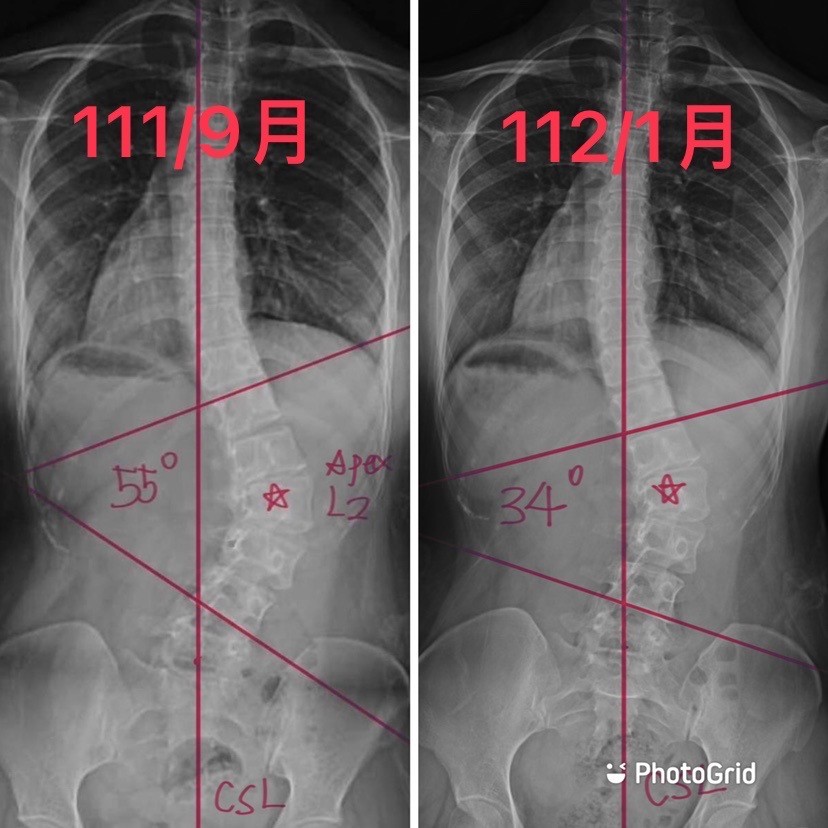

個案小茹(化名),還記得9月初的初次評估,雖然年齡已超過25歲,角度更是來到55度

但歷經4個月的努力,每天按時的矯正運動

不僅解決下背的痠痛!

角度大幅降低整整21度!!!

體態也越來越理想!(瘦了瘦了)